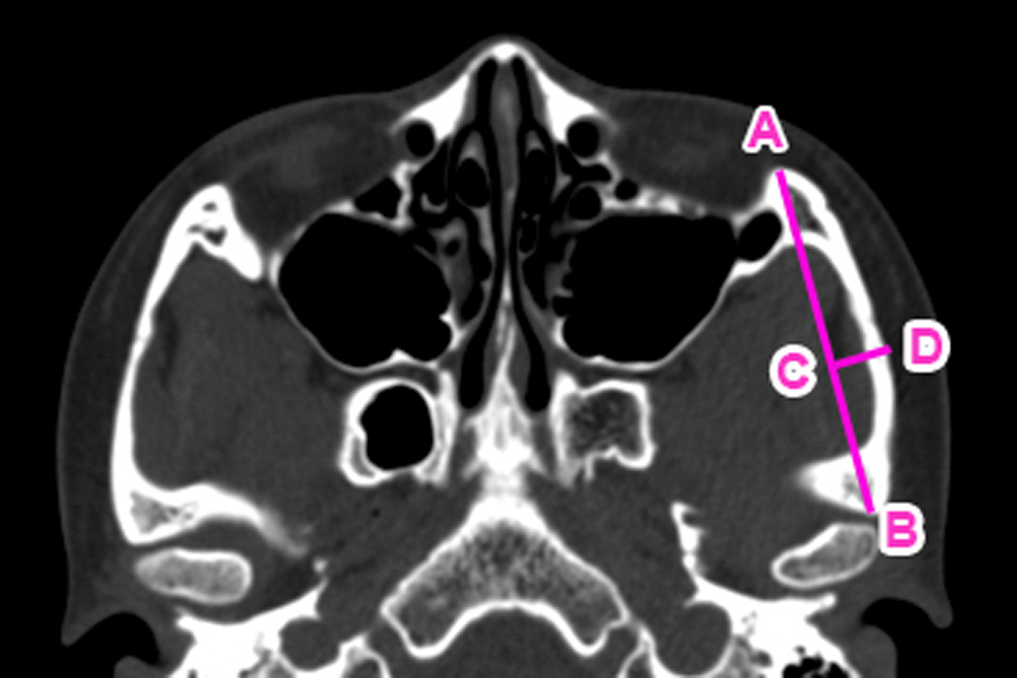

A digitalized CT image was used to estimate the arch height and the length of bone for removal from the zygomatic arch. A specific piece of bone was removed from…